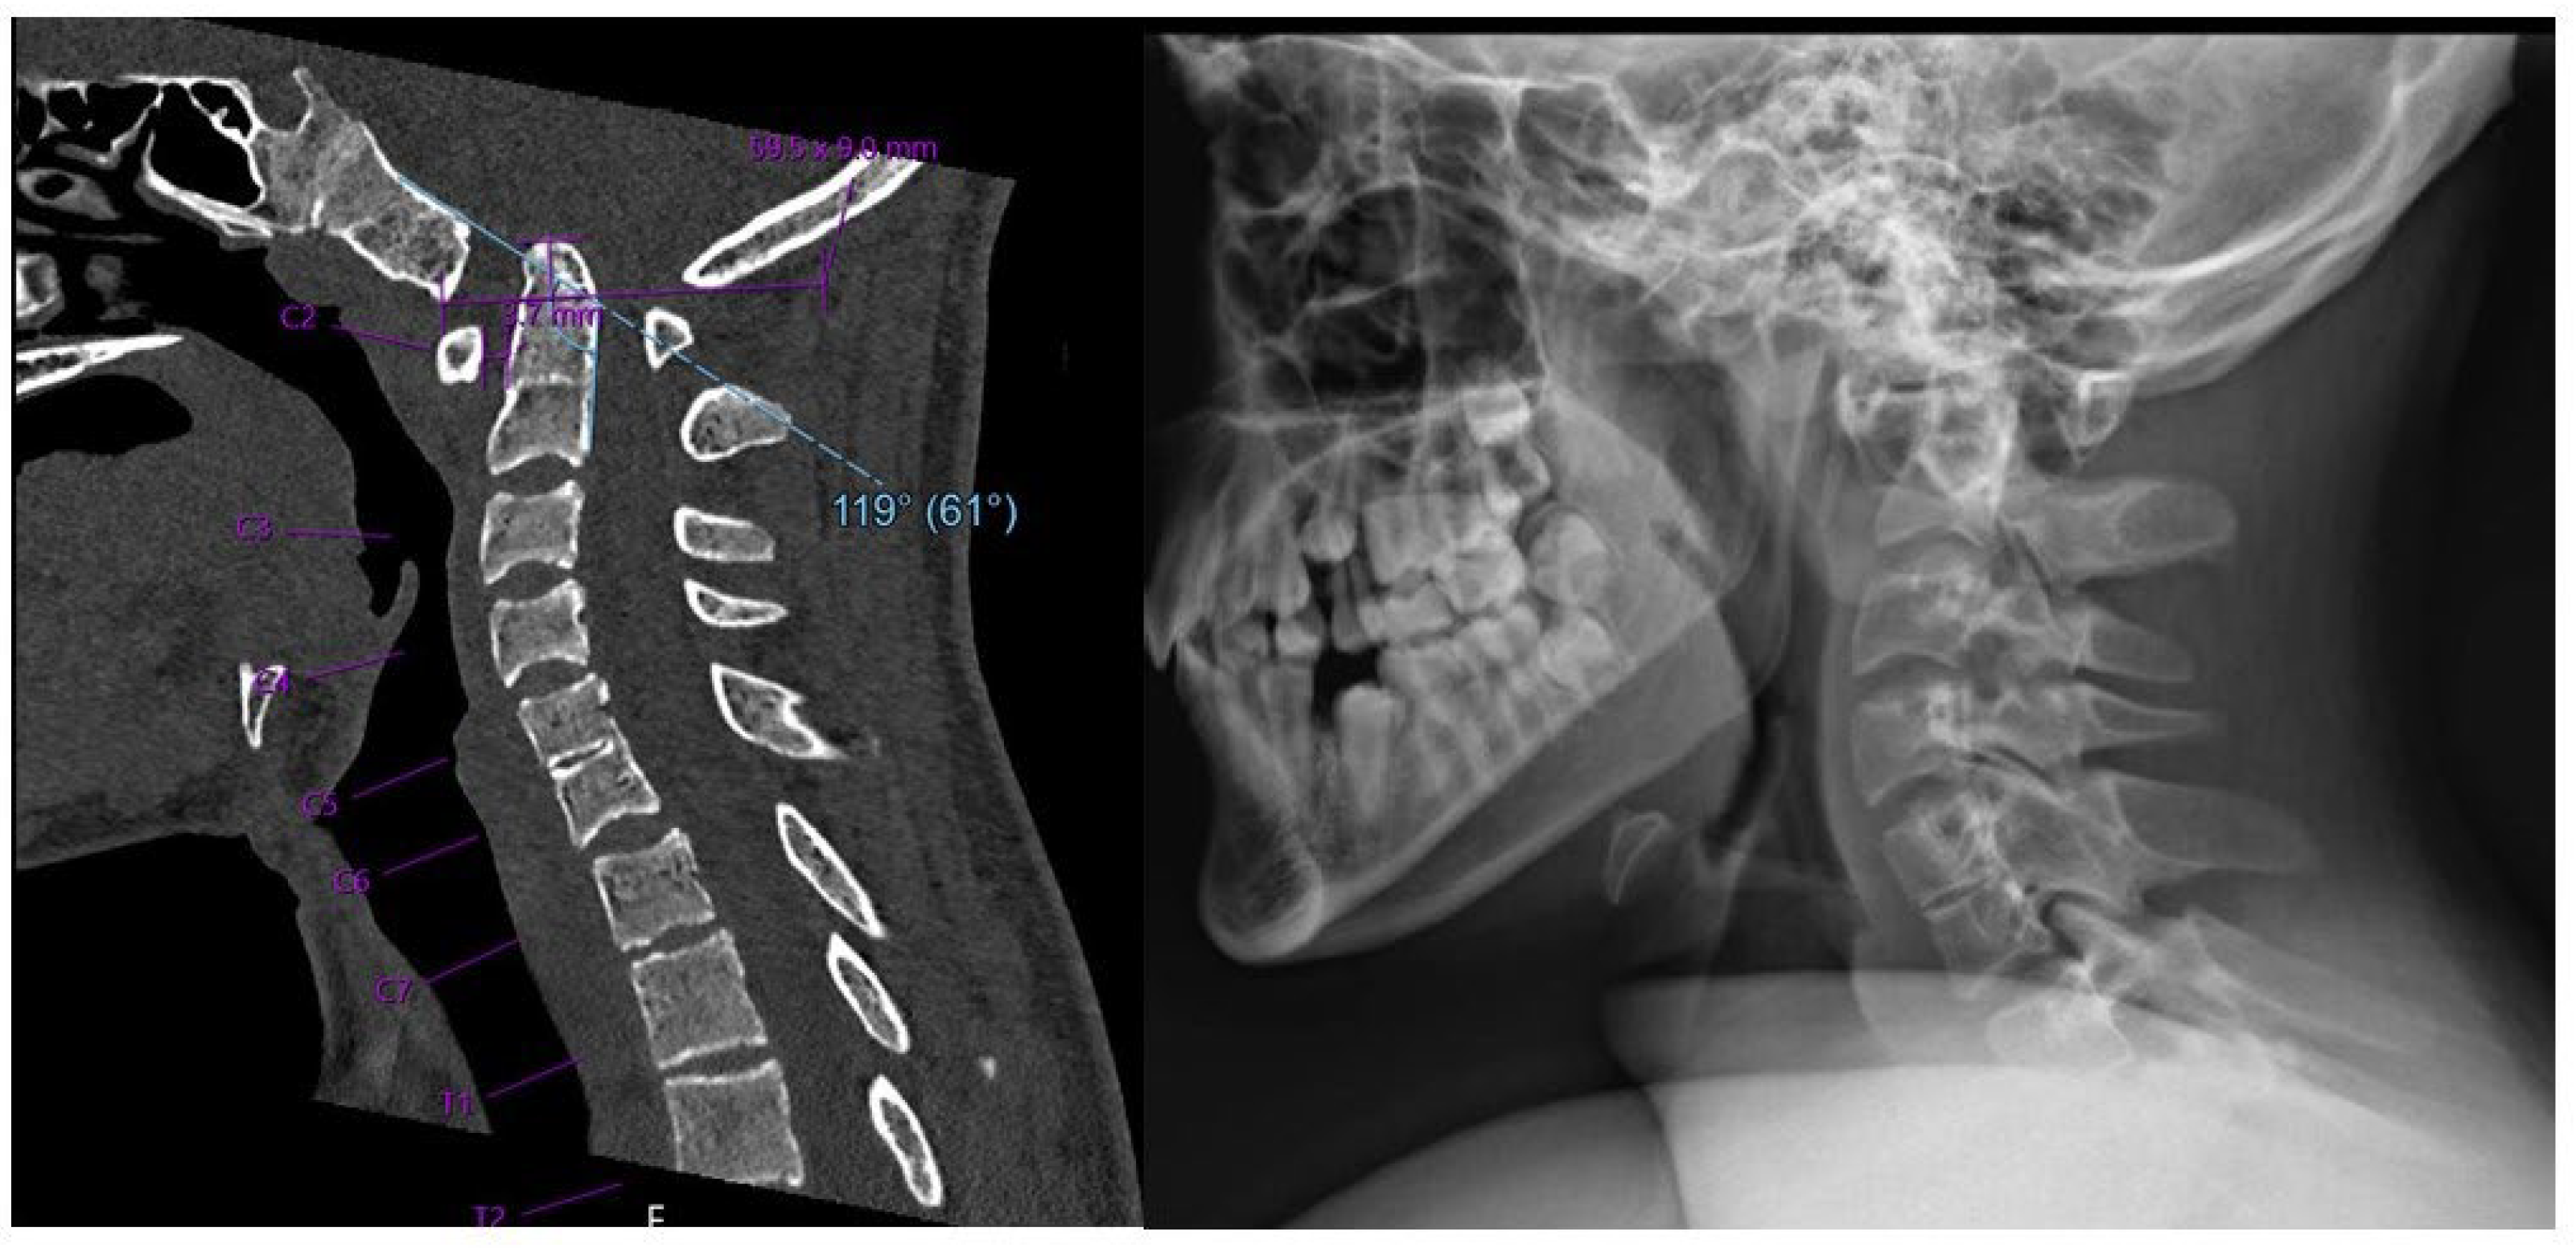

2.2. Imaging and Diagnosis